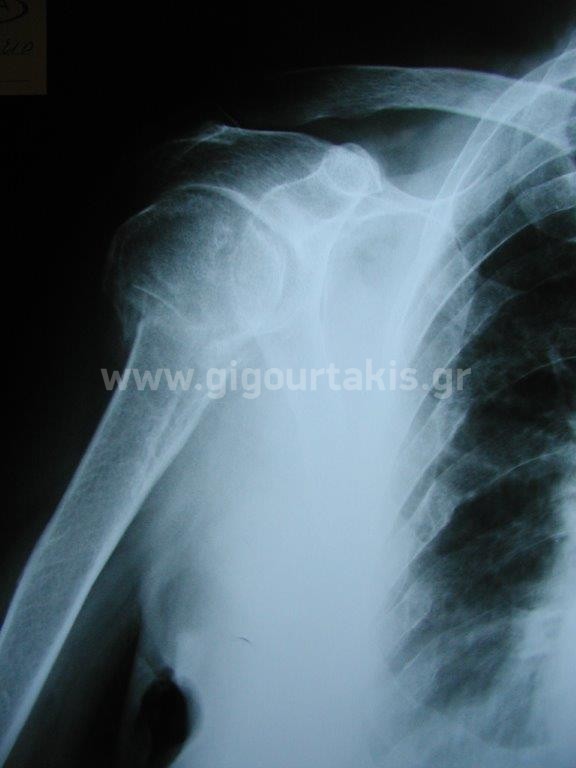

ΚΑΤΑΓΜΑ ΒΡΑΧΙΟΝΙΟΥ ΚΑΤΑΓΜΑ ΥΠΟΚΕΦΑΛΙΚΟ ΣΥΝΤΗΡΗΤΙΚΑ ΠΕΡΙΣΤΑΤΙΚΟ 1 01. 02. 03.ΑΡΧΙΚΗ ΑΠΑΓΩΓΗ ΩΜΟΥ 04.ΑΡΧΙΚΗ ΕΞΩ ΣΤΡΟΦΗ ΩΜΟΥ 06.ΑΡΧΙΚΗ ΕΣΩ ΣΤΡΟΦΗ ΩΜΟΥ 11.ΤΕΛΙΚΗ ΑΠΑΓΩΓΗ ΩΜΟΥ 12.ΤΕΛΙΚΗ ΟΠΙΣΘΙΑ ΠΡΟΣΑΓΩΓΗ ΩΜΟΥ 14.ΤΕΛΙΚΗ ΕΣΩ ΣΤΡΟΦΗ ΩΜΟΥ ΠΕΡΙΣΤΑΤΙΚΟ 2 01. 02. 04.ΑΡΧΙΚΗ ΑΠΑΓΩΓΗ ΒΡΑΧΙΟΝΙΟΥ 05.ΑΡΧΙΚΗ ΕΞΩ ΣΤΡΟΦΗ ΒΡΑΧΙΟΝΙΟΥ 06.ΑΡΧΙΚΗ ΟΠΙΣΘΙΑ ΠΡΟΣΑΓΩΓΗ ΒΡΑΧΙΟΝΙΟΥ 07.ΤΕΛΙΚΗ ΚΑΜΨΗ ΩΜΟΥ 2 08.ΤΕΛΙΚΗ ΑΠΑΓΩΓΗ ΩΜΟΥ 1 10.ΤΕΛΙΚΗ ΕΞΩ ΣΤΡΟΦΗ ΩΜΟΥ 2 11.ΤΕΛΙΚΗ ΟΠΙΣΘΙΑ ΠΡΟΣΑΓΩΓΗ ΩΜΟΥ 1 ΠΕΡΙΣΤΑΤΙΚΟ 3 01 Στις κατηγορίες:ΑΝΩ ΑΚΡΟ, ΣΥΝΤΗΡΗΤΙΚΑ, ΚΑΤΑΓΜΑ ΥΠΟΚΕΦΑΛΙΚΟ ΒΡΑΧΙΟΝΙΟΥ, ΚΑΤΑΓΜΑ ΒΡΑΧΙΟΝΙΟΥ, ΩΜΙΚΗ ΖΩΝΗ ΒΡΑΧΙΟΝΙΟ, ΚΑΤΑΓΜΑTA